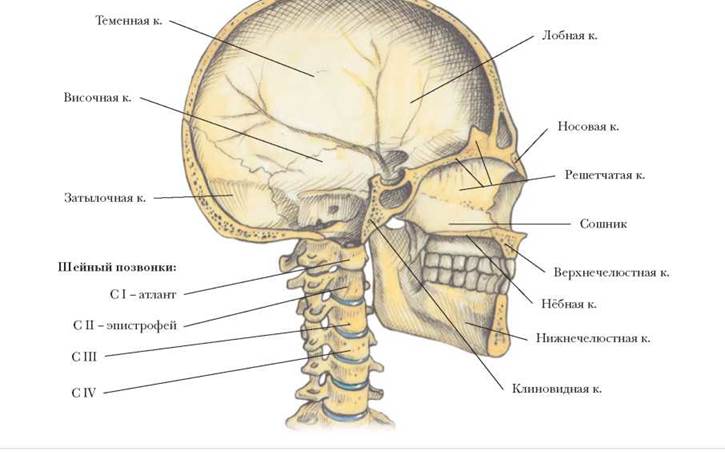

Анатомические изображения срединной сагиттальной линии черепа